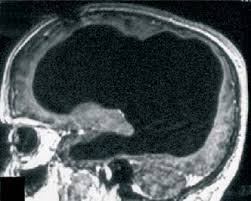

1. Femeia fără cerebel

Jumătate din numărul total de neuroni se află în cerebel, dar se pare că putem trăi fără cerebel fără să ştim acest lucru.

O femeie din China, în vârstă de 24 de ani, a dus o viață destul de normală până să fie internată într-un spital după ce a acuzat ameţeli şi greaţă. Cu această ocazie, aceasta a făcut prima sa tomografie craniană care a evidenţiat lipsa totală a cerebelului, o regiune a creierului responsabilă pentru menţinerea echilibrului, coordonarea mişcărilor, abilitatea de a învăța mişcări noi și controlul vorbirii.

În locul unde ar fi trebuit să se afle cerebelul nu exista decât un spaţiu gol.

Cercetătorii nu sunt încă siguri cum a supraviețuit femeia în toți acești ani fără cerebel, dar sugerează că aceasta şi-ar fi pierdut cerebelul la o vârstă fragedă, atunci când alte părţi ale creierului ei au putut compensa lipsa acestuia. Această caracteristică este cunoscută sub numele de plasticitatea creierului, adică capacitatea de adaptabilitate a acestuia.

Se pare că în absenţa cerebelului, creierul femeii a utilizat alte regiuni cerebrale care au preluat funcţiile cerebelului.